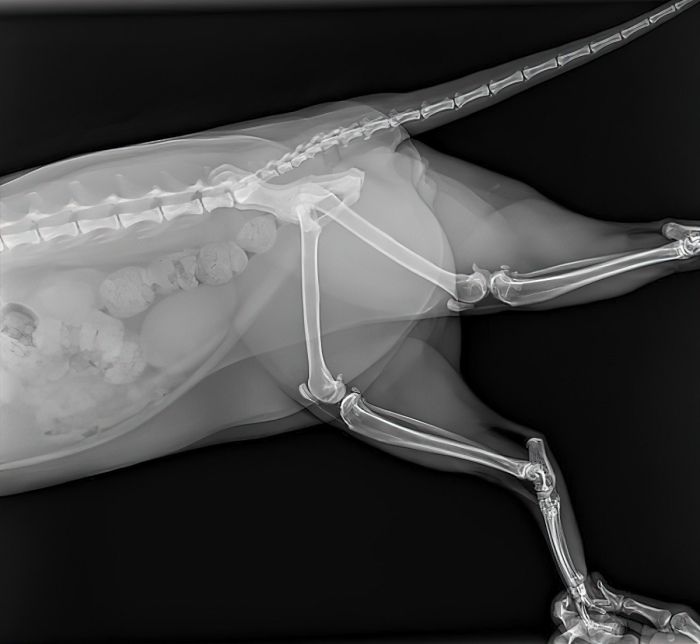

Кота срочно доставили к ветеринару. У него нашли несколько ушибов, два сломанных когтя и нос, опухший в результате столкновения со стеклом, но никаких опасных для жизни травм. И это несмотря на то, что он своей тушкой пробил заднее стекло автомобиля!